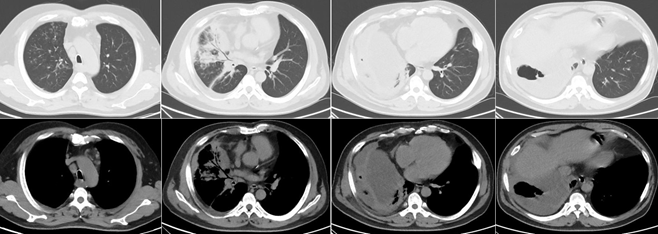

4月20日胸部CT:左上肺大实变渗出影(图8)

图片

图8  患者胸部CT(2020年4月20日)

• 5月17日胸部CT:左肺病灶较前明显吸收,右肺上叶病变较前缩小(图9)。

图9  患者胸部CT(2020年5月17日)

• 7月24日门诊复查胸部CT:病灶基本吸收,残留少许条索影和莫玻璃影(图10)

图10 患者胸部CT(2020年7月24日)

• 2021年3月24日门诊复查胸部CT:病灶较前进一步吸收好转(图11)

图11  患者胸部CT(2021年3月24日)